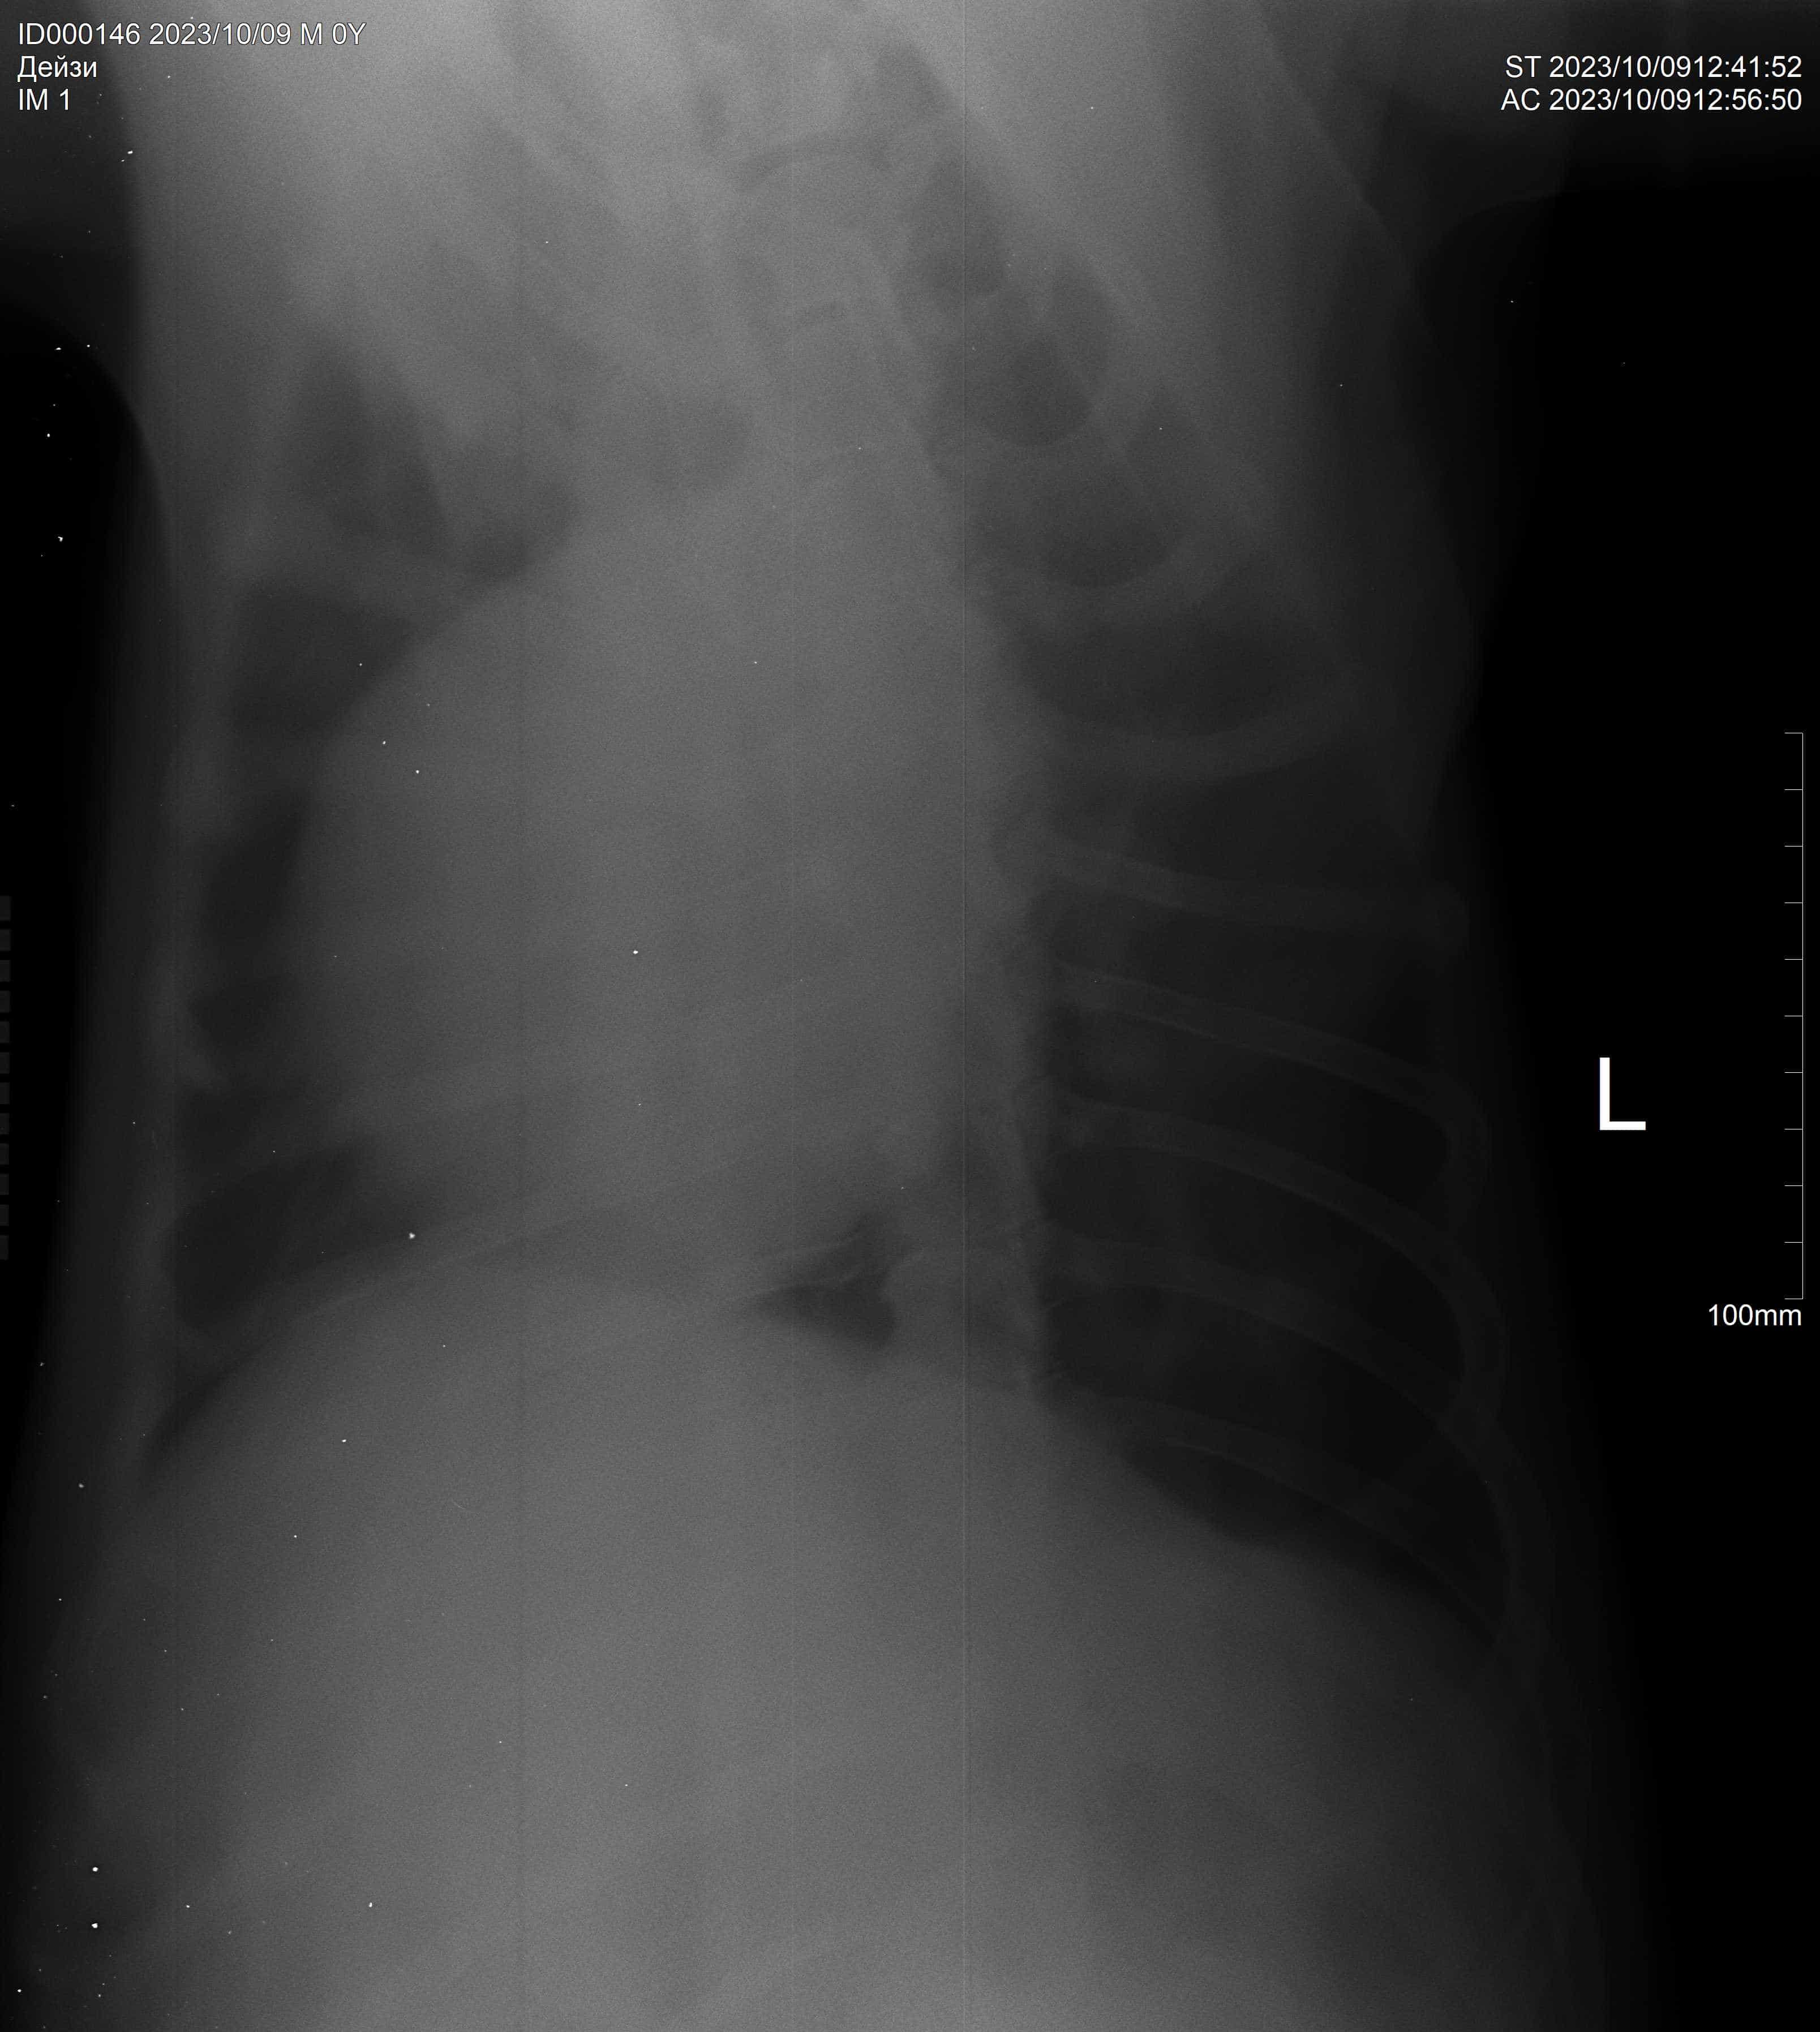

Операция и кардиография

Выписка после операции